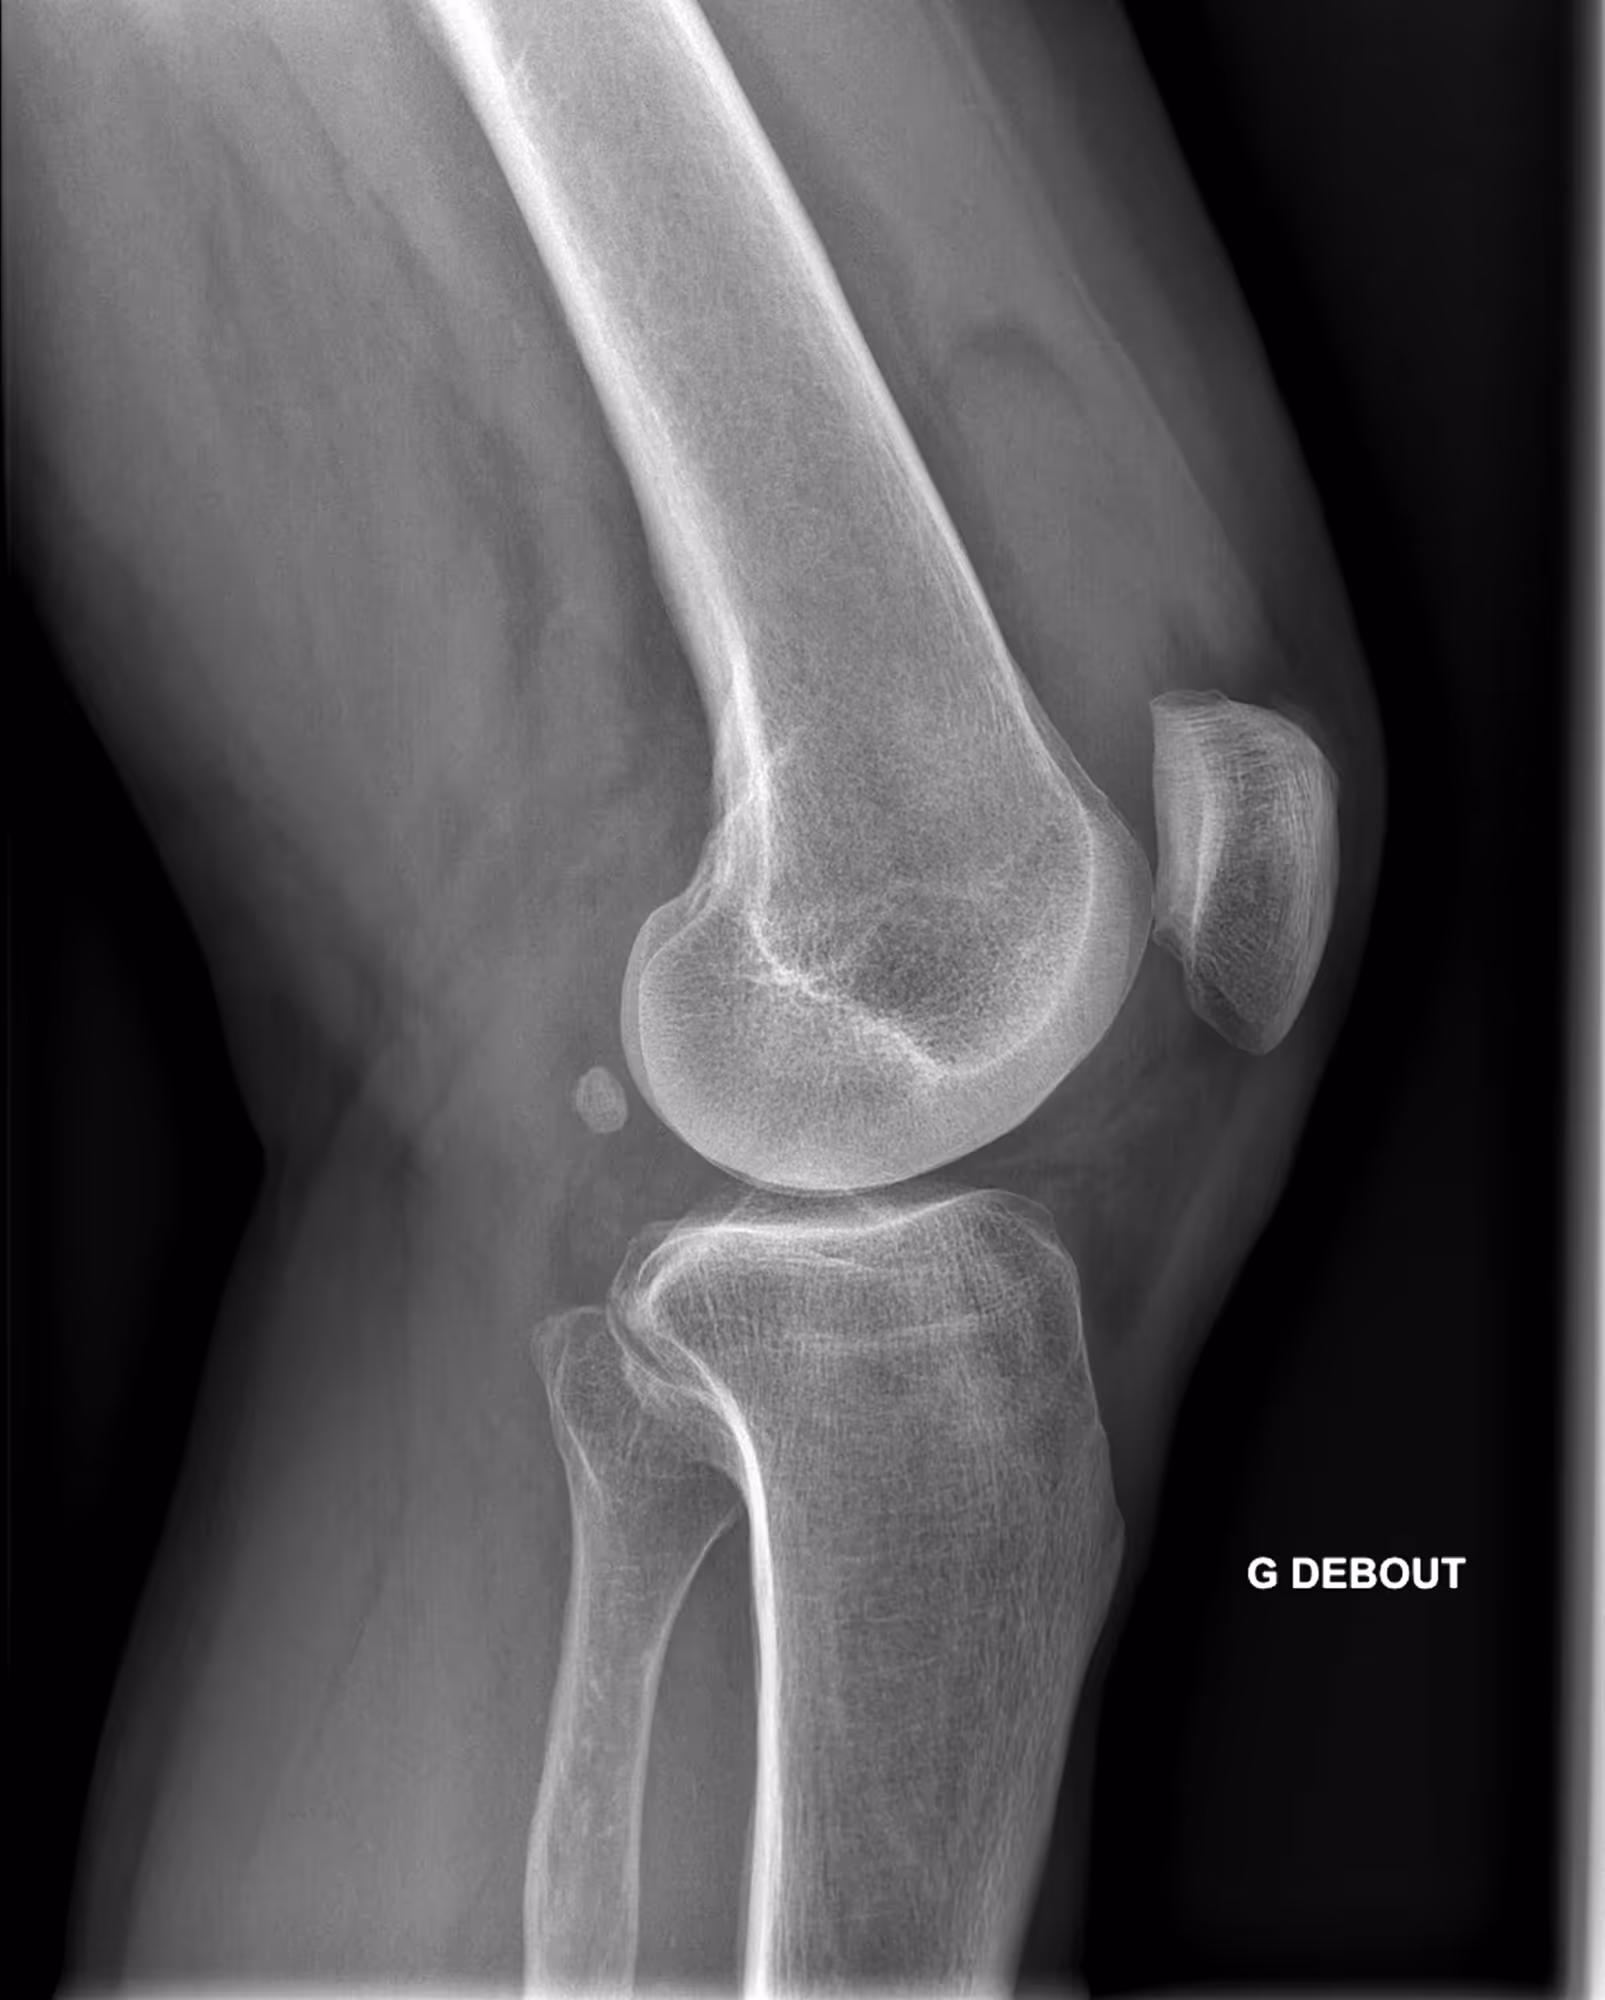

A 63-year-old male with lingering pain after a trail run.

Results

BoneView detected a fracture of the lateral tibial plateau and associated effusion. The fracture has a high risk of displacement.